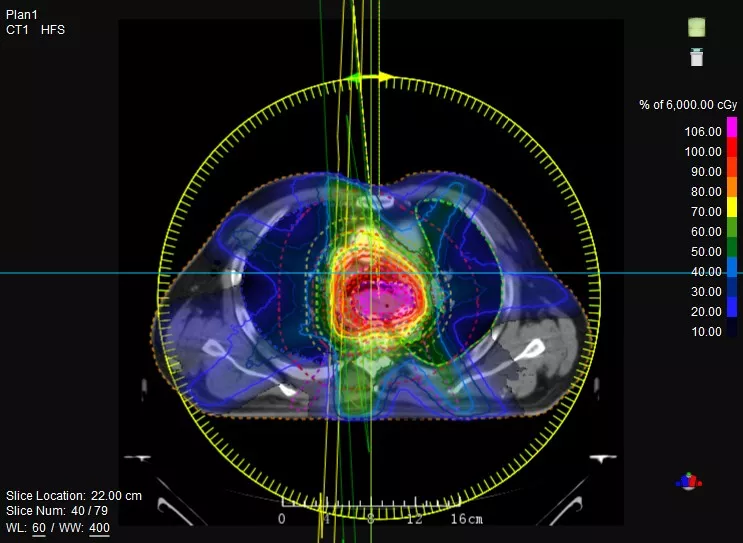

機(jī)載CT影像可直接用于放療計劃制作

CT-IGRT配準(zhǔn),除骨性標(biāo)記外,還能以器官、軟組織等作為參考,真正找到配準(zhǔn)目標(biāo)

鼻咽癌患者,進(jìn)行旋轉(zhuǎn)容積調(diào)強(qiáng)治療(uARC)